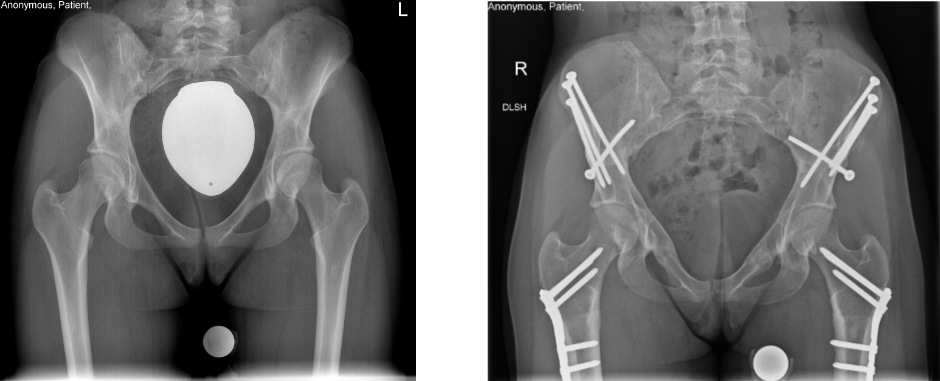

Die operative Therapie der Pfannendachdysplasie zielt auf eine Reduktion der Druck- und Scherbelastung des knöchernen und weichteiligen Pfannenrandes. Hierzu führen wir eine Dreifach-Beckenosteotomie (die sog. Triple-Osteotomie nach Tönnis und Kalchschmidt) durch, bei der die Hüftgelenkspfanne aus dem Beckenknochen durch drei „Knochenschnitte“ herausgelöst, in eine biomechanisch günstigere Position gedreht und in dieser mit Schrauben fixiert wird. Dieser Eingriff zieht eine verbesserte Hüftkopfüberdachung nach sich.

In besonders gelagerten Fällen muss dieser Eingriff mit einer sog. intertrochantären bzw. subtrochantären Osteotomie, einem „Knochenschnitt“ am Oberschenkelknochen, verknüpft werden, um eine noch günstigere Biomechanik für das betroffene Hüftgelenk zu erzielen.

Der „Goldstandard“ in der Behandlung des femoroazetabulären Impingements stellt die chirurgische Hüftluxation dar. Nach dem Ausrenken des Hüftkopfs aus der Hüftgelenkspfanne ist eine optimale Sicht auf beide Gelenkpartner möglich, die eine sorgfältige Behandlung aller Aspekte eines femoroazetabulären Impingements erlaubt. Um den Hüftkopf aus der Hüftgelenkspfanne ausrenken zu können, ist in einem ersten Operationsschritt die Ablösung des grossen Rollhügels (Trochanter major) vom Oberschenkelknochen nötig (Trochanter-Flip-Osteotomie). Der abgelöste Trochanter major wird am Ende der Operation mit zwei Schrauben refixiert, um das Wiederanheilen zu ermöglichen.